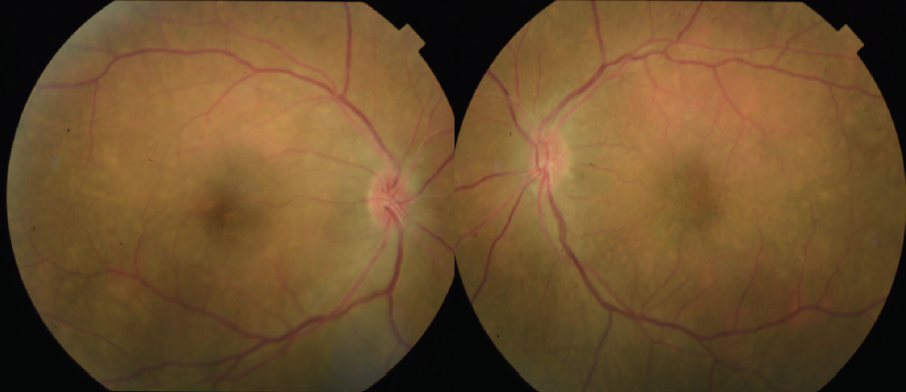

The patient showed a robust initial response to steroids with significant improvement in her vision and anatomy. Within 1 week, her VA had improved to 20/100 OD and 20/70 OS. Fundus examination showed improvement with less defined lesions (Figure 4), and OCT showed significant reduction in fluid (Figure 5). After 1 month of treatment, her vision had improved to 20/50 OD and 20/40 OS, with further improvement seen on fundus findings (Figure 6) and near complete resolution of fluid on OCT (Figure 7). Continued improvement was seen 6 weeks after steroid therapy was initiated (Figure 8 and Figure 9). The marked improvement in structure and function with oral prednisone treatment, without ATT treatment, led to a presumed diagnosis of VKH disease.

Figure 8. Color fundus photos 6 weeks after initiation of oral prednisone steroids show improvement.